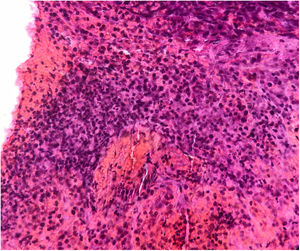

Se realizó una biopsia con sacabocados que mostró un tumor de células pequeñas basófilas, con poco citoplasma, cromatina y núcleo prominente, y células dispuestas en capas a lo largo del grosor de la dermis sin compromiso epidérmico (fig. 2). El estudio inmunohistoquímico fue positivo para CD99, PKC, y vimentina, y negativo para actina, desmina, S100, cromogranina, CD20, C3 y CK20. La TAC torácica reveló un nódulo sólido de naturaleza no cálcica de 5mm en la base del pulmón izquierdo, sospechoso de metástasis, además de paquipleuritis izquierda. La TAC abdominal mostró hepatomegalia a expensas del lóbulo derecho, sin dilatación del conducto biliar, no se observaron masas sólidas ni quísticas en el parénquima; además, se detectó esplenomegalia con una imagen heterogénea hipodensa de tamaño no mayor a 25mm, también sospechosa de metástasis. Se diagnosticó un tumor neuroectodérmico primitivo tipo sarcoma primario cutáneo de Ewing. La paciente fue referida a un hospital donde recibió un ciclo de inducción con vincristina y doxorrubicina, logrando una reducción del 50% de la masa. Este fue seguido de 2 ciclos de vincristina ya que se agotaron los suministros. El sangrado se presentó con el tercer ciclo, por lo que se indicó radioterapia (acelerador lineal). Seis meses más tarde, se obtuvo una reducción del 90% de la lesión cutánea (fig. 3). Desgraciadamente la paciente falleció 2 semanas después de la última cita en dermatología.

Histológicamente, estos sarcomas están constituidos principalmente por células tumorales pequeñas y redondas que, por lo general, expresan CD99 y positividad débil para marcadores de sinaptofisina.3,5–8. Algunos tumores pediátricos de células pequeñas y redondas con afectación cutánea pueden descartarse fácilmente mediante inmunohistoquímica. El rabdomiosarcoma puede exhibir positividad para CD99 y también tiñe marcadores musculares, como la desmina, miogenina y myo-D1, lo que no sucede con los tumores de la familia del sarcoma de Ewing4,5,8. El linfoma linfoblástico puede afectar a la piel y frecuentemente es positivo para CD99 y también para TdT, mientras que el tumor de la familia del sarcoma de Ewing es siempre negativo para este último2,4,5,7.